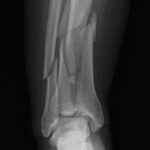

¿Sufres de dolor crónico en el tobillo que limita tus actividades diarias? Es posible que hayas escuchado sobre el reemplazo articular del tobillo y la osteotomía correctiva del calcáneo. Estas son dos procedimientos quirúrgicos que pueden ofrecer alivio a muchas personas.

Este procedimiento se suele recomendar para pacientes con artritis avanzada, lesiones graves o deformidades en el tobillo que no responden a tratamientos más conservadores.

El calcáneo es el hueso más grande del tobillo y del pie. Una osteotomía correctiva del calcáneo implica realizar un corte en este hueso para realinearlo y corregir deformidades que causan dolor o inestabilidad en el tobillo.

Esta cirugía se utiliza para tratar condiciones como el pie plano, el pie cavo o las fracturas mal consolidadas del calcáneo.

En algunos casos, tanto el reemplazo articular del tobillo como la osteotomía correctiva del calcáneo pueden realizarse en la misma cirugía. Esto suele ocurrir cuando el paciente presenta una combinación de artritis y deformidades en el tobillo.